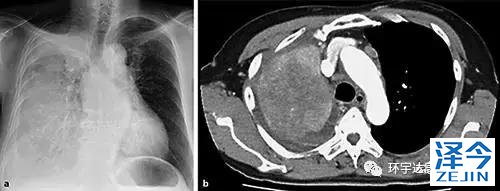

六十五岁女士由于右胸痛及劳累性呼吸困难而来医院检查。CT扫描显示右上叶和右胸腔积液中有巨大肿块(图1 b)。另外,左肺,肝,左肾上腺以及纵隔淋巴结肿大也发现多个肿块。

图1a显示右肺渗透性降低的胸片。b胸部的CT图像显示右肺和右胸腔积液中的巨大肿块